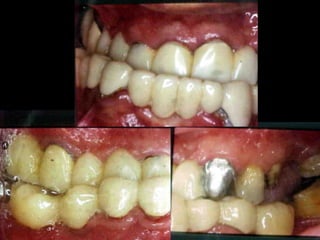

Modelos PreoperatoriosModelos Preoperatorios

Arcada Superior:

Forma oval

Paladar profundo

Totalidad de órganos dentarios a excepción de tercer molar izq.

Restauraciones deficientes

Arcada Inferior:

Forma ovalada

Colapso posterior

Ligero apiñamiento de anteriores

Rotación de premolares

Modelos vista lateral

prequirúrgica

Clase III molar y caninaClase III molar y canina